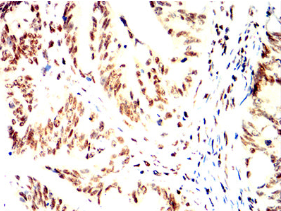

IHC    1/200 - 1/1000